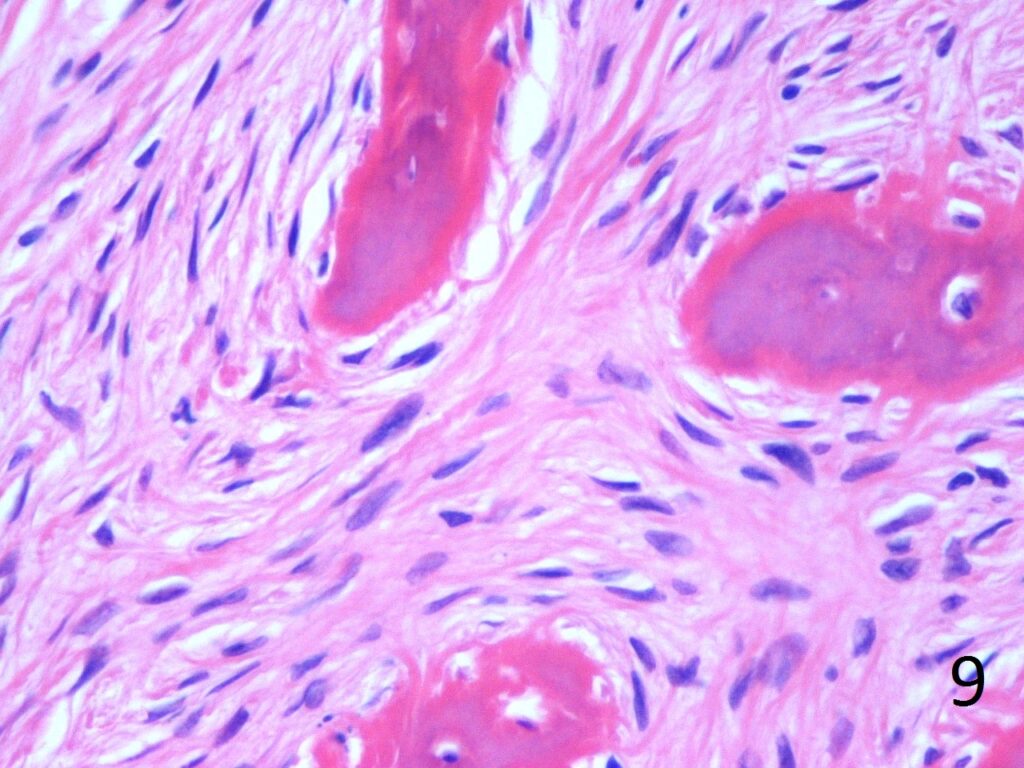

• Metaplastic chondroid component could be associated, but not common to be related with cartilaginous neoplasm

• No cytologic atypia is seen

Fig. 9. High power photograph of pathology of fibrous dysplasia shows woven bone being produced by the fibrous tissue. There are no osteoblasts lining the bone.